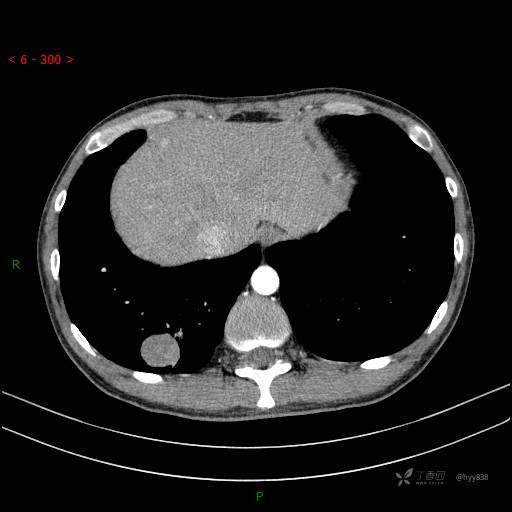

增强动脉期